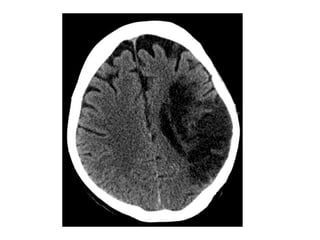

c) Hemorrhage :

-Frank hemorrhage into an arterial infarct

typically occurs a few days after the initial

stroke

-If there is hemorrhage within an infarct from

the outset , a venous stroke or arterial

embolus should be considered

-Hemorrhagic transformation with foci of hemorrhage

at the right post central gyrus

CT , Hemorrhagic evolution of initial ischemic infarction with

significant midline shift